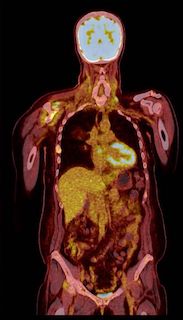

PET CT

PET CT